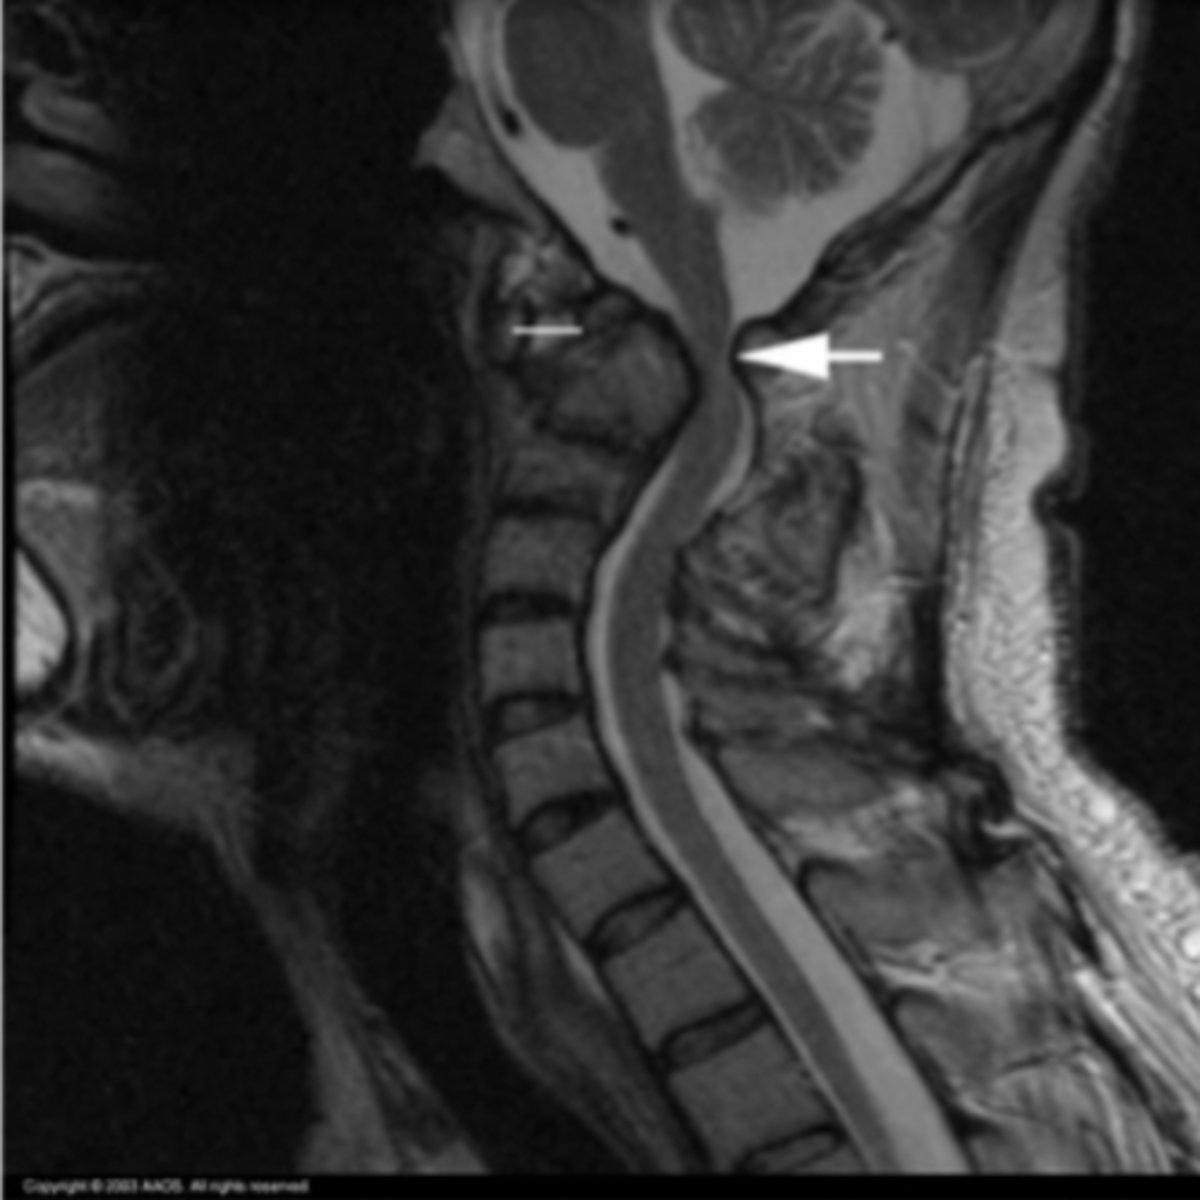

Rheumatoid Arthritis of Cspine

What is the issue?